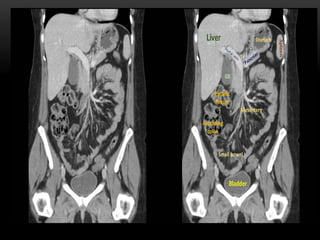

CT cross sectional

anatomy.